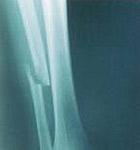

X-ray of a fracture A single fracture is when a bone is broken in just one place. You may have heard the term hairline fracture. This is a single fracture that is very small, like the width of a hair. A complete fracture is when the bone comes apart.

X-rays are taken to see the break. Treatment depends on the kind of fracture that is identified.